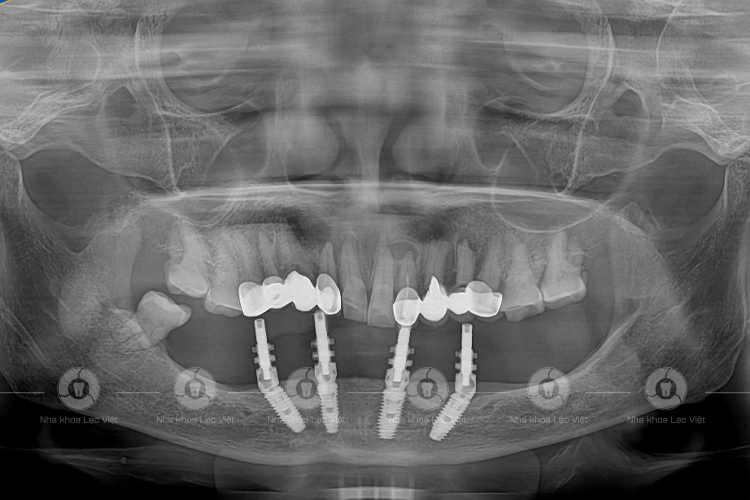

Ảnh chụp phim sau cấy implant của khách hàng Đàm Thị Bén (Ảnh: Nha khoa Lạc Việt)

Bác sĩ Nguyễn Văn Luyến – Người trực tiếp lên kế hoạch điều trị cho cô Đàm Thị Bén cho biết: “Trường hợp của cô Bén là một ca phức tạp, trước khi cấy ghép implant, chúng tôi sẽ  phải nhổ bỏ các chân răng còn sót lại, sau đó tính toán vị trí đặt trụ implant sao cho tránh các dây thần kinh xoang hàm. Nếu như chỉ phụ thuộc vào tay nghề của bác sĩ thì rất khó có thể đảm bảo chính xác tuyệt đối, tuy nhiên, ở Lạc Việt, chúng tôi có sự hỗ trợ của các công nghệ, máy móc như: Công nghệ Safe-tech, máy phẫu thuật từ tính,… nên việc xác định vị trí sẽ nhanh và chính xác hơn”.